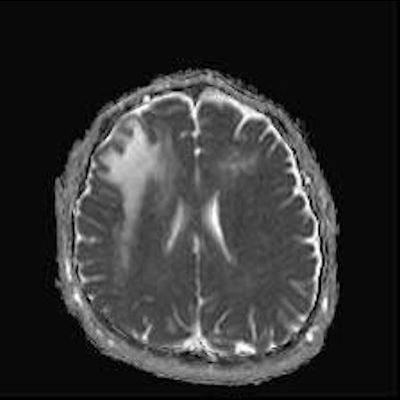

1. A) Aksiyel T2A görüntülerde bilateral sağda belirgin frontoparietal subkortikal ve derin periventriküler beyaz cevherde subkortikal U fiberleri boyunca yerleşimli sinyal artımları (oklar) izlendi.  Tarifli alanlar aksiyel T1A serilerde hipointens görünümde (oklar) izlendi.

1. PML’de MRG bulguları genellikle multifokal, asimetrik periventriküler ve subkortikal beyaz cevher tutulumu şeklindedir. Subkortikal U-fiberleri sıklıkla tutulur, özellikle parietooksipital bölgelerde belirgin lezyon eğilimi vardır.

2. T1 ağırlıklı görüntülerde tutulan bölgeler hipointens, T2A’da ise hiperintens izlenir. Ana lezyon çevresinde çok sayıda noktasal (milkyway) sinyal artımları görülebilir. Ayrıca spleniumu çaprazlayan parietooksipital sinyal değişiklikleri (barbell bulgusu) ve dentat nukleusu koruyarak serebellar beyaz cevher tutulumu (shrimp bulgusu) da tanımlanmıştır.

4. Bizim hastamızda bilinen HIV enfeksiyonu mevcuttu ve yapılan kraniyal MR görüntülemede multifokal, asimetrik, periventriküler ve subkortikal beyaz cevherde yerleşimli, kitle etkisi göstermeyen ve kontrastlanmayan lezyonlar izlendi. Lezyonların subkortikal U-fiberleri tutması ve özellikle parieto-oksipital bölgelerde belirgin olması nedeniyle ön planda PML düşünüldü. Histopatolojik tetkik ile PML tanısı doğrulandı.